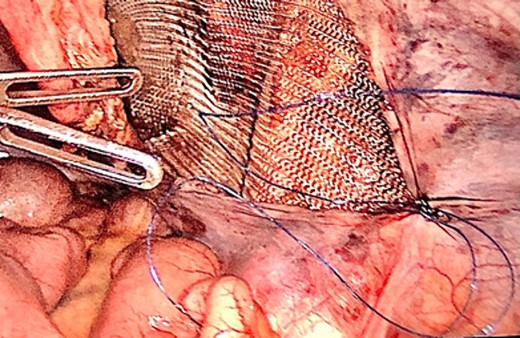

The hernia sac was found to invaginate the right inguinal ring, and after drawing back the hernia sac, the atrophic testis, along with the spermatic cord and testicular vessels, was revealed (Fig. 4). Heavyweight mesh was used (Fig. 5). The operative time was 95 min. No complications were noted and the patient was discharged on postoperative day 2. Pathological examination revealed no malignancy or spermatogenic abilities. No improvement in the semen analysis results was noted during the follow-up period. To date, there has been no recurrence of the hernia.

Laparoscopic view of the peritoneal suture in the TAPP procedure performed after orchiectomy.